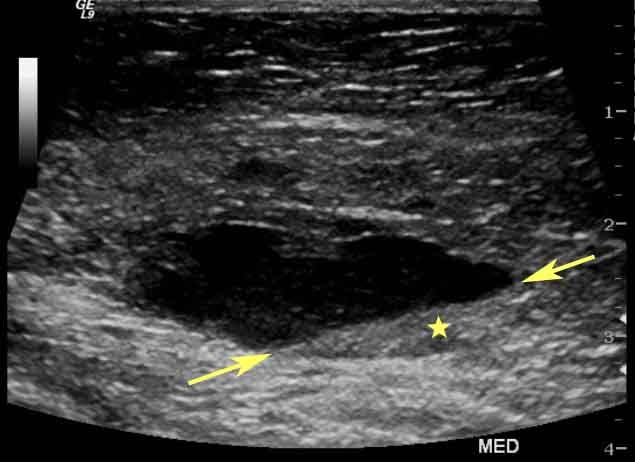

El ultrasonido mamario, también conocido como ecografía mamaria, utiliza ondas sonoras de alta frecuencia para generar imágenes detalladas del tejido mamario. Este método es especialmente útil para visualizar estructuras internas, como quistes, tumores sólidos y anomalías en mujeres con tejido mamario denso.

El propósito principal del ultrasonido mamario es complementar otros estudios, especialmente cuando la mamografía presenta limitaciones. Es particularmente eficaz para distinguir entre masas sólidas y líquidas, como en el caso de quistes. Además, su capacidad para guiar procedimientos invasivos, como biopsias, lo convierte en una herramienta indispensable en el diagnóstico y tratamiento de enfermedades mamarias.

- Evaluación de anomalías detectadas en mamografía o exploración clínica: Cuando una masa o irregularidad es identificada, el ultrasonido ayuda a caracterizarla con mayor precisión.

- Confirmación y localización de lesiones: En pacientes con masas detectadas, el ultrasonido ayuda a confirmar la presencia de la lesión y determinar si es sólida o líquida.